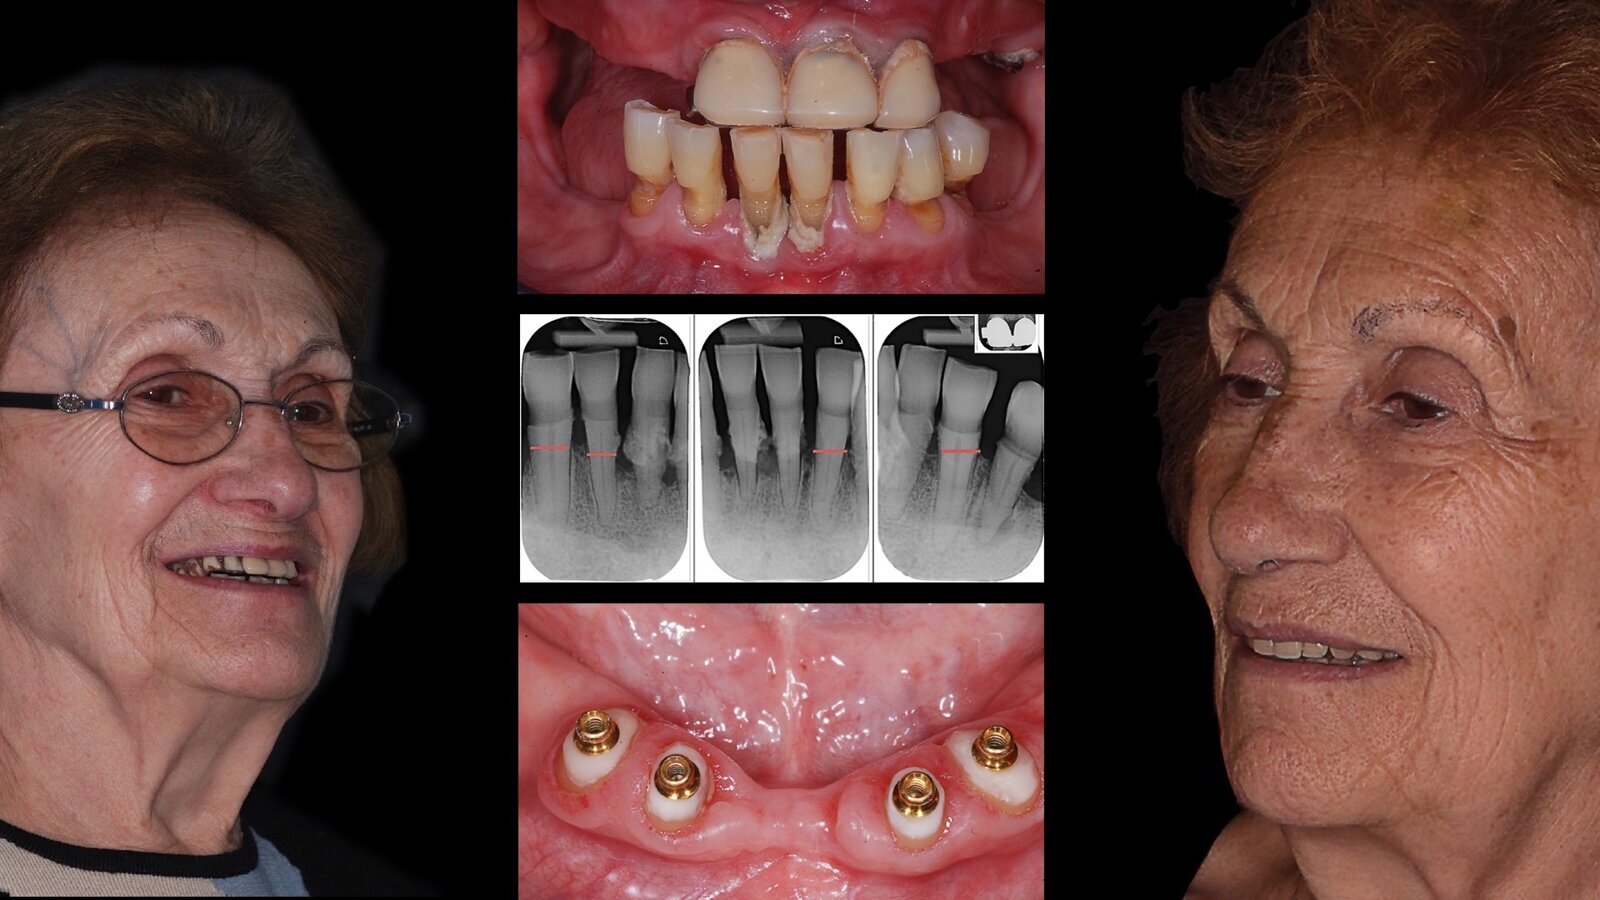

Imagen inicial y final de la paciente y varios de los pasos del tratamiento realizado para su rehabilitación.

Figuras 1 - 2. Caso clínico de una paciente femenina de 79 años edéntula en los sectores posteriores de la mandíbula y portadora de un esquelético removible en el arco superior. Pidió una mejora de la estética y la función, rehabilitando ambos maxilares, sin recurrir a la inserción de implantes por razones económicas.

Su historial médico muestra que la paciente no está afectada por ninguna patología sistémica y que no es fumadora. En el examen extraoral es evidente la pérdida de la dimensión vertical que enfatiza la presencia de las arrugas periorales y la imperfección ligada a la sonrisa inversa.

Figuras 3 - 4. El examen objetivo intraoral y las evaluaciones radiográficas muestran que los dientes residuales del maxilar superior son candidatos a la extracción, mientras que algunos en la mandíbula mantienen suficiente apoyo radicular residual para asegurar que permanezcan en boca. En particular, se considera que los elementos 4.3, 4.2, 3.2, 3.3 se pueden mantener. El plan terapéutico, por lo tanto, prevé la confección de dos prótesis totales con soporte mucoso y en 4 raíces mandibulares para garantizar una adecuada retención.